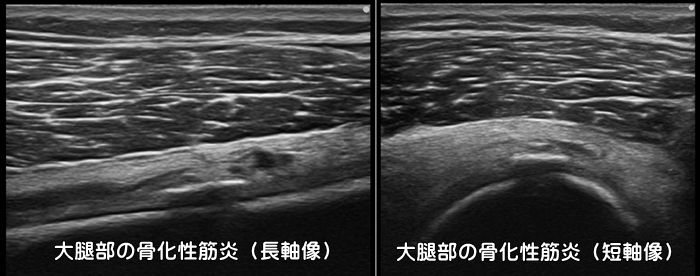

骨化性筋炎(異所性骨化)

サッカーやラグビーなどのコンタクトスポーツで主に大腿の前面を強打(ももかん)すると筋肉内に血の塊である血腫(けっしゅ)が形成されます。その後痛みを我慢して無理に運動したりすることで血腫内にカルシウムが異常に集積し、本来あるはずのない所に骨が作られます。(異所性骨化)筋肉の中に骨ができてしまうと運動時の痛みや圧痛、可動域の制限などが出現します。安静が重要で、重症例ではスポーツ復帰に6ヶ月以上は必要です。レントゲンでは骨化が確認できるまでに1ヶ月程必要ですが、エコーでは早期に確認可能です。